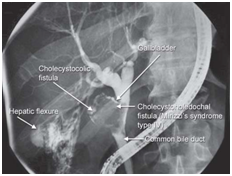

Figure 6 Mirizzi Syndrome.

Mirizzi (Figure 6)